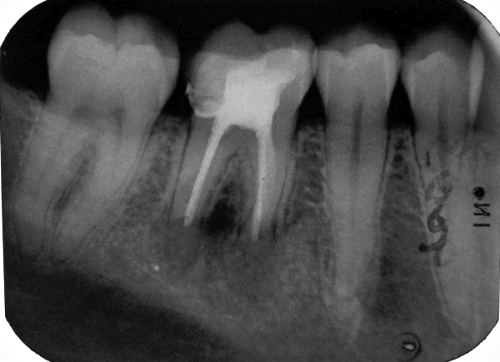

Fall 1:

Messaufnahme anlässlich der Revision mit absichtlichem Überinstrumentieren in die Aufhellung im Dezember 2007 (Klick!)